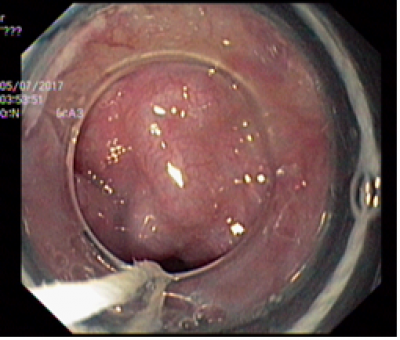

Nội soi thực quản dạ dày, điều trị giãn tĩnh mạch thực quản

Nội soi có giá trị quan trong trọng việc chẩn đoán xác định giãn tĩnh mạch thực quản, phân loại mức độ và vị trí giãn và can thiệp hiệu quả.